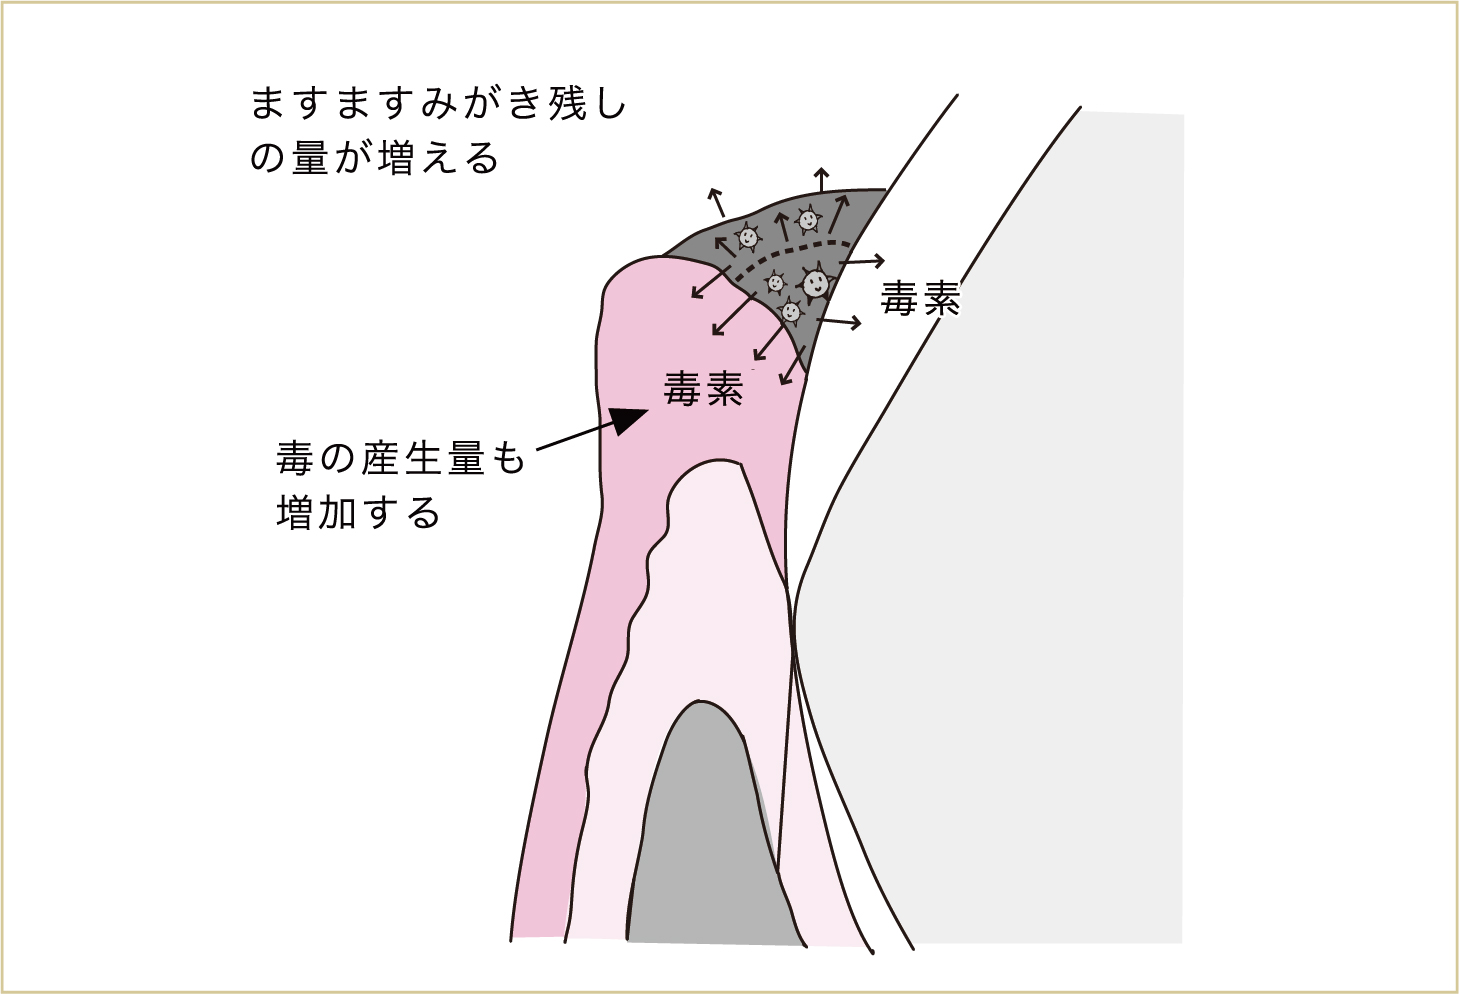

歯肉が腫れることで、歯と歯肉の間の溝が深くなったりして、よりみがき残しができやすい状態になります。

そうして、ますます汚れが降り積もった結果、細菌たちが出す毒素の量も増加します。増加した毒素を洗い流すための血液も、さらにたくさん必要になってくるため、よりいっそう腫れてきます。

腫れた歯肉は、ますます汚れがつきやすく、みがき残しができやすい形になっていき、より多くの細菌による毒素が歯肉に影響を与えるようになる。